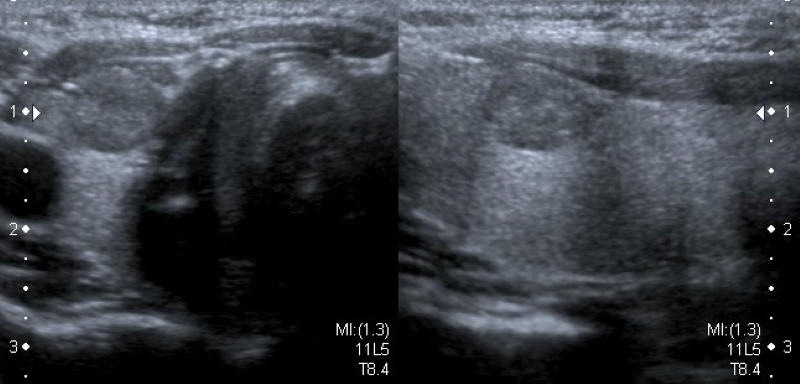

Ecogenicidad

Refiere al grado de ecogenicidad (no calcificado ni quístico) que presenta el nódulo respecto al parénquima tiroideo: hiperecoicos (Fig. 9), isoecoicos (Fig. 10) e hipoecoicos (Fig. 11). En el caso de los nódulos muy hipoecoicos (Fig. 12) se realiza la comparación con la ecogenicidad de los músculos adyacentes.

Si bien los nódulos malignos son más frecuentemente hipoecoicos, también lo son muchos nódulos histológicamente benignos20. Según la literatura los nódulos muy hipoecoicos presentan mayor riesgo de malignidad2,13,16, pero esta característica ha sido descripta solo en la población adulta.

En caso de nódulos con componente sólido y quístico la ecogenicidad debe describirse en relación con la porción sólida, con el fin de no confundir el término heterogéneo con el componente mixto sólido y quístico.

También podemos diferenciar los nódulos en homogéneos (Fig. 13) o heterogéneos (Fig. 14). Estos últimos contienen áreas con diferente ecogenicidad, y para poder brindar más información descriptiva es necesario mencionar el patrón predominante.